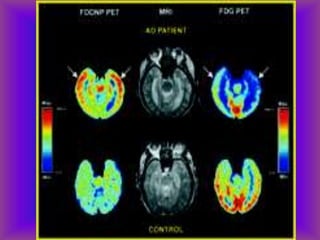

Uses for SPECT and PET

• Acute stroke

• Identify a seizure focus-increased

flow during sz and decreased

interictal flow

• Dementia-frontal pattern in FTLD,

temporo-parietal pattern in AD

• Ligand imaging in PD, others

• 98.

Uses for SPECTand PET • Acute stroke • Identify a seizure focus-increased flow during sz and decreased interictal flow • Dementia-frontal pattern in FTLD, temporo-parietal pattern in AD • Ligand imaging in PD, others